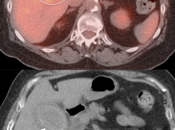

PET/CT Interpretation of Gallbladder Activity:

The normal gallbladder typically demonstrates little or no FDG uptake.

Mild to moderate diffuse gallbladder uptake is usually normal.

Intense diffuse gallbladder uptake in an otherwise normal appearing gallbladder often represents normal physiologic uptake. Ultrasound correlation, however, is still typically recommended: “Ultrasound correlation may be of diagnostic value, if clinically warranted.”

Diffuse intense gallbladder uptake associated with wall thickening, pericholecystic fluid or gallstones is suspicious for cholecystitis. In such cases, ultrasound correlation is strongly recommended, “Ultrasound correlation is recommended in this case to exclude acute cholecystitis.”

While focal intense gallbladder wall uptake can be seen with benign polyps, adenomyomatosis or focal inflammation associated with cholecystitis, malignancy must be excluded.